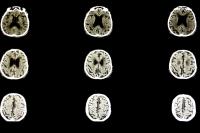

In this trial, 255 patients with primary or secondary progressive MS were randomized to receive oral ibudilast or placebo for almost two years. The patients ranged in age from 18 to 65, with an average disease duration of 12 years. Using magnetic resonance imaging, the researchers found that patients taking ibudilast had 48 percent less brain atrophy compared with controls. The drug was well tolerated but was associated with higher rates of gastrointestinal side effects, headache, and depression than placebo.

This study looked at brain volume, not symptoms. However, brain shrinkage in MS is usually associated with declines in physical and cognitive function. “We can detect brain volume changes more accurately than changes in physical or cognitive function, which is why the study used brain volume change as the primary outcome,” explains Riley. “This allowed us to obtain results over a shorter period of time with fewer patients. Further studies are needed to determine if ibudilast has any effect on symptoms or neurologic disability.”